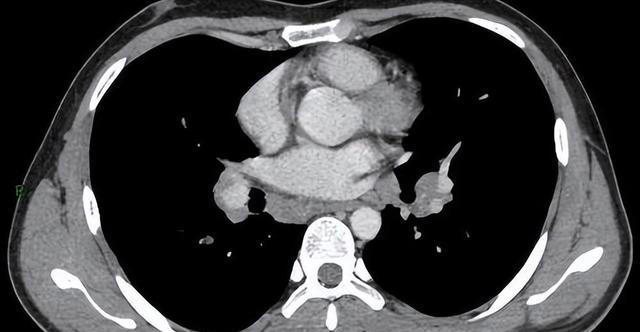

第三个:报告出现"纵隔或肺门淋巴结肿大",或者"伴阻塞性肺炎、肺不张"

这两类描述比前两种更需要重视,原因在于它们说明的不仅仅是结节本身的问题,而是病变对周围结构已经产生了影响。

肺门和纵隔是肺部的"核心地带",淋巴结分布密集,参与免疫应答。感染或炎症确实可以引起淋巴结短暂肿大,消炎后恢复,这属于正常范畴。

但如果淋巴结肿大明显、多发、结构紊乱,且伴随其他异常,需要警惕肿瘤转移的可能性。肺癌一旦出现淋巴结转移,分期已不再是早期,治疗选择和预后都会受到直接影响。

阻塞性肺炎和肺不张是另一个角度的警示信号。二者出现的根本原因,通常是气道某处发生了堵塞,气体无法正常通过,导致远端肺组织出现炎症或萎缩。堵塞物可能是肿瘤,也可能是异物,不管哪种情况,都需要进一步支气管镜或增强CT来明确原因。

有一种情况要特别留意,就是某个肺叶的肺炎反复发作,治疗后好转,过段时间又出现在同一个位置,这种"固定性肺炎"背后很可能有支气管腔内病变,不能一次次当普通感冒处理就算了。